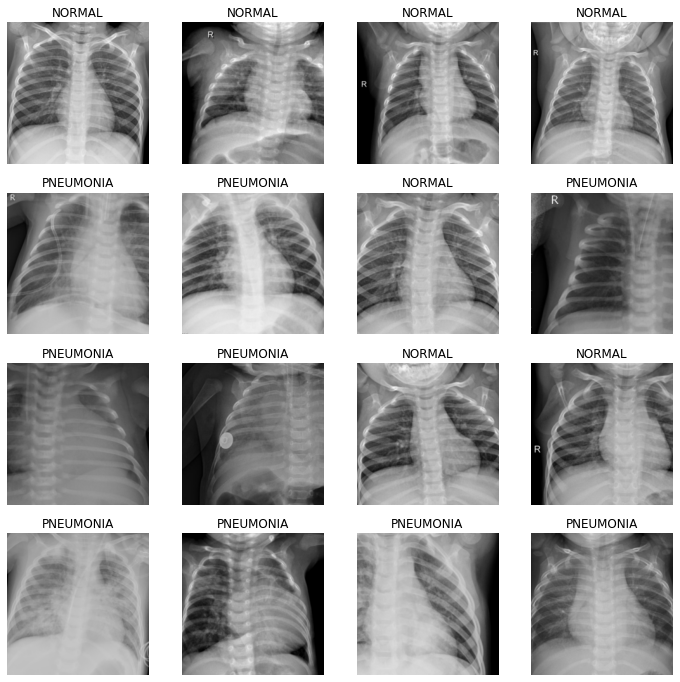

files=get_image_files(path)dls = ImageDataLoaders.from_folder(path, train='train', valid_pct=0.2, item_tfms=Resize(224)) dls.vocab['NORMAL', 'PNEUMONIA']

dls.show_batch(max_n=16)